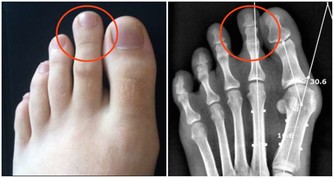

肝主筋,又能藏血。這句話其實就是在告訴我們,從指甲上的狀態上就能看出肝血的盛衰。

肝臟的健康狀態與指甲的關係非常密切,

我們從指甲的堅脆、厚薄和顏色等方面,就能讀出體內肝血盛衰的秘密。

通常,我們不需要仔細觀察自己的十指,只要單獨觀察食指就可以了。

1、看顏色正常的指甲顏色是肉色的,如果我們的食指指甲發白的話,

那就說明我們的肝血並不是特別旺盛,已經出現了肝血虛的症狀。

如果我們的指甲顏色是暗黃色的,那就很可能是肝膽疾病的先兆。

2、看紋路一般來說,食指的指甲上是很少會出現紋路的。如果我們的指甲上出現了橫溝,那說明肝臟的營養不良。

而指甲上出現了縱紋,那就說明最近的身體比較虛弱,我們一定要注意休息。

3、看斑點身體健康,指甲上是不會出現任何斑點的。如果食指的指甲上出現白色的斑點,說明我們的肝臟機能出現了損傷。

如果指甲的下方出現了紅色斑點,說明肝血循環不暢,肝臟甚至有病變的可能。